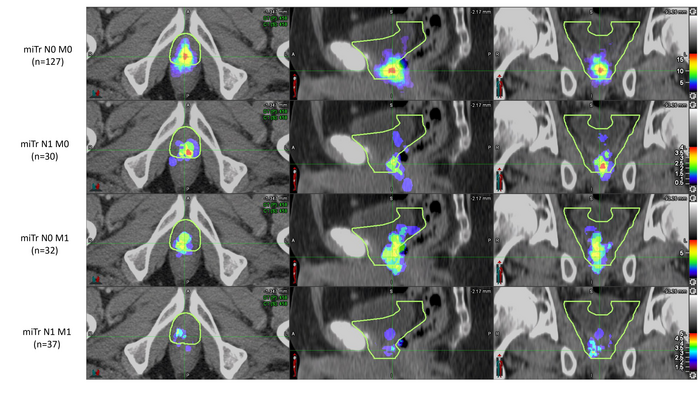

Prostate cancer patients who experienced biochemical recurrence after radical prostatectomy were included in the analysis if their PSMA PET/CT imaging showed recurrence in the prostate bed. To analyze the patterns of recurrence, two nuclear medicine physicians documented the areas of recurrence on the PSMA PET/CT, and four radiation oncologists (masked to the PSMA PET/CT findings) delineated the clinical target volume using RTOG guidelines on the CT images of the PET/CT. PSMA recurrence locations were then compared to the RTOG-based clinical target volumes.

PSMA recurrences were fully covered by the clinical target volumes in 54 percent of the patients. In 34 percent of the patients, PSMA recurrence was only partly covered, and in 13 percent of patients the PSMA recurrence was located fully outside of the clinical target volume.

“This study has the potential to redefine prostate bed contouring guidelines to improve the therapeutic ratio for patients receiving postoperative radiotherapy,” said Ida Sonni, MD, project scientist in the Department of Radiology at the University of California, Los Angeles. “Nuclear medicine and molecular imaging advances, such as PSMA PET, have the ability to guide individualized, tailored treatments that will ultimately benefit all our patients.”